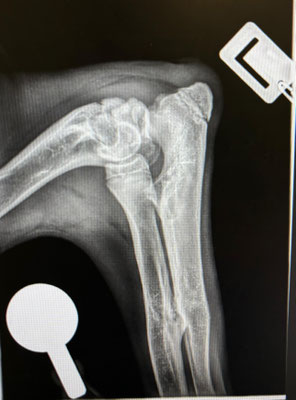

Im September 2025 haben wir Ihnen die kleine Finija vorgestellt: Gerade einmal vier Monate alt, wurde sie in einem erschütternden Zustand gefunden. Beide Hinterbeine waren gebrochen, eine Fortbewegung war für sie nur noch auf den Vorderpfoten möglich. Trotz starker Schmerzen zeigte Finija eine unglaubliche Willenskraft – ein kurzes Video aus…